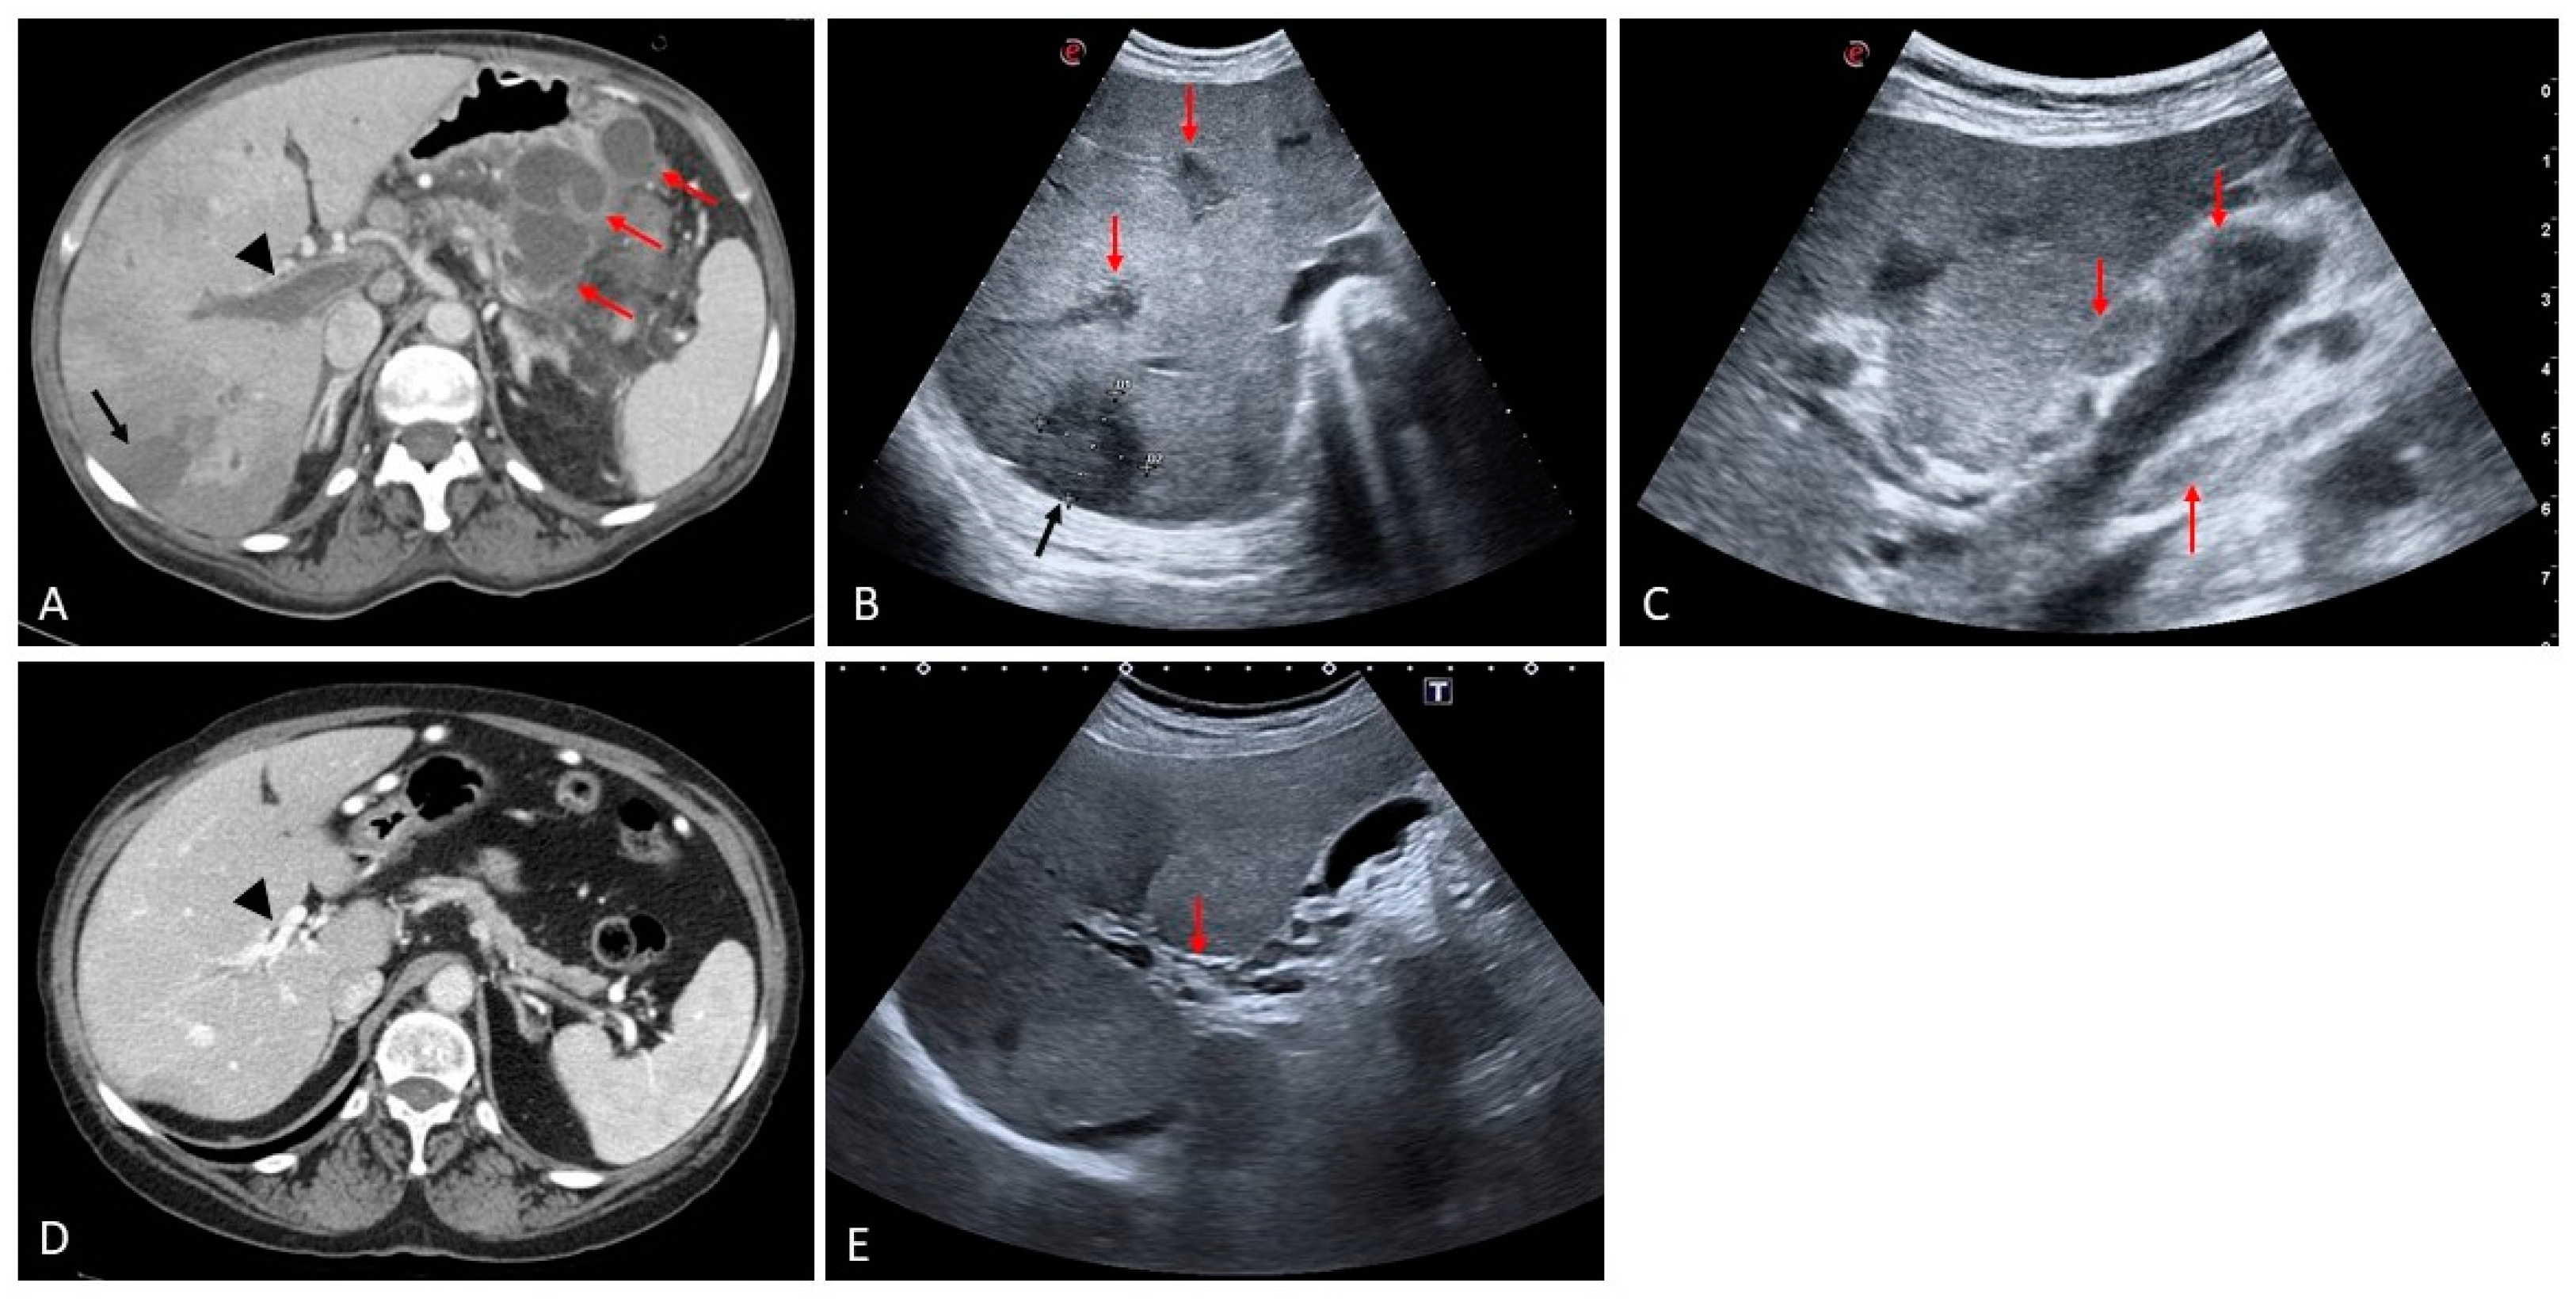

2. Portal Vein Thrombosis

- (i)

- the presence of primary or secondary liver malignancy and echogenic material filling the portal venous lumen;

- (ii)

- the diameter of the lumen of the portal vein is often increased according to the growth of the tumor within the vessel;

- (iii)

- evidence of vascularization of the thrombus as a consequence of neoplastic neoangiogenesis [1].